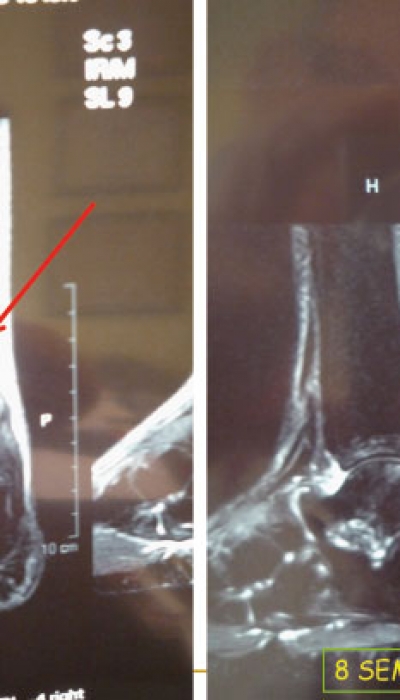

PRP